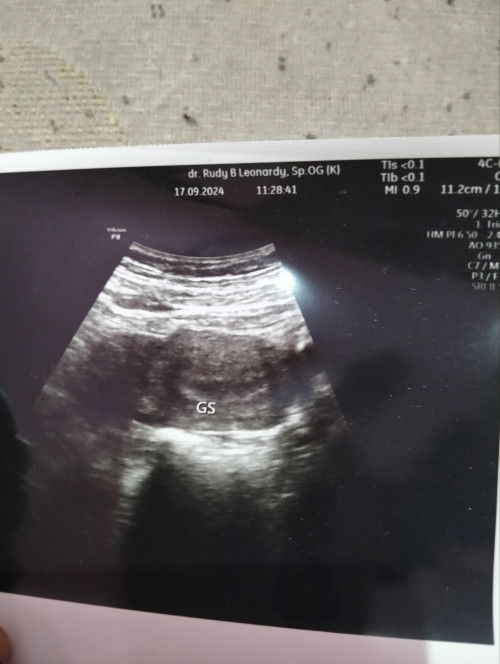

Bun inikan udah telat 6 hari jadi saya USG ke dokter apakah ini udah hamil ya? KRNA aq PNY riwyt ket

pas usg dokternya diem aja kah bu. ga jelasin apaยฒ ?

disuruh DTG lagi 2 Minggu kemudian